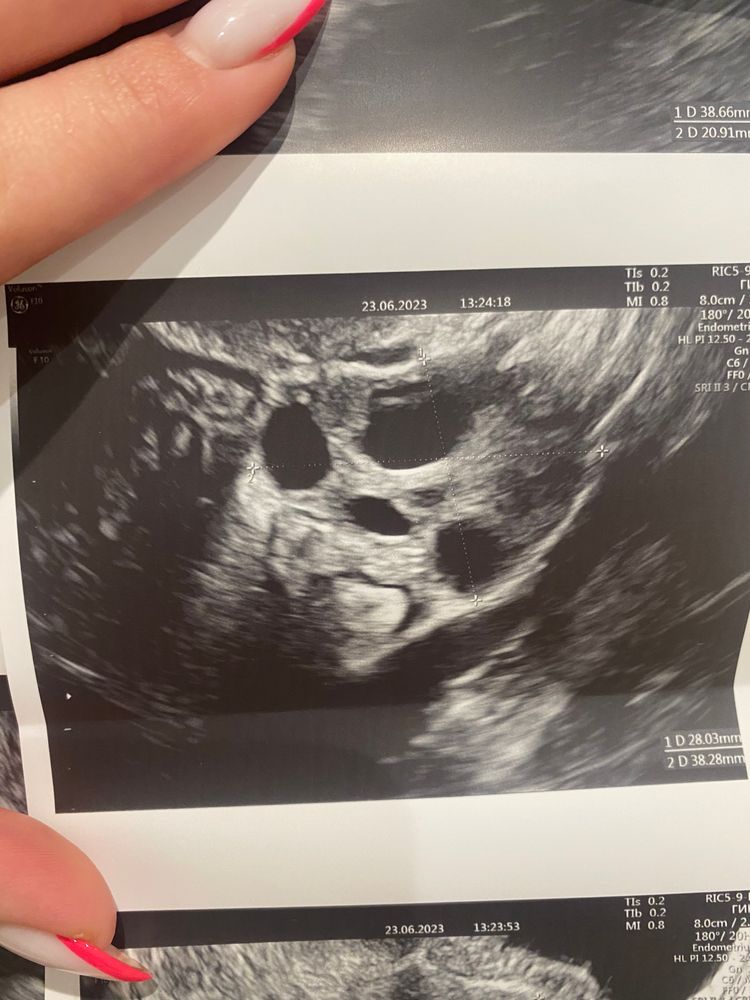

Девочки , подскажите пожалуйста кто разбирается в узи

Да нет никаких кист, это доминантный фолликул. Размер 19х17. Нормальный преовуляторный фолик. У меня таких фоток тьма, желтое тело вообще по другому выглядит

Это не жёлтое тело. Это дф. Отслеживали овуляцию по УЗИ несколько месяцев и жёлтое тело оно конечно совсем другое.

По-моему у вас фолликулярная киста, судя по узи яичника и по эндометрию

Девочки че то с мамой поговорила и за переживала климакс в 36 лет у неё тип начался( УЗИ после бхб. Киста, эндометриоз?